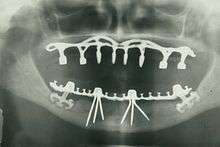

Panoramic radiograph of historic dental implants, made 1978